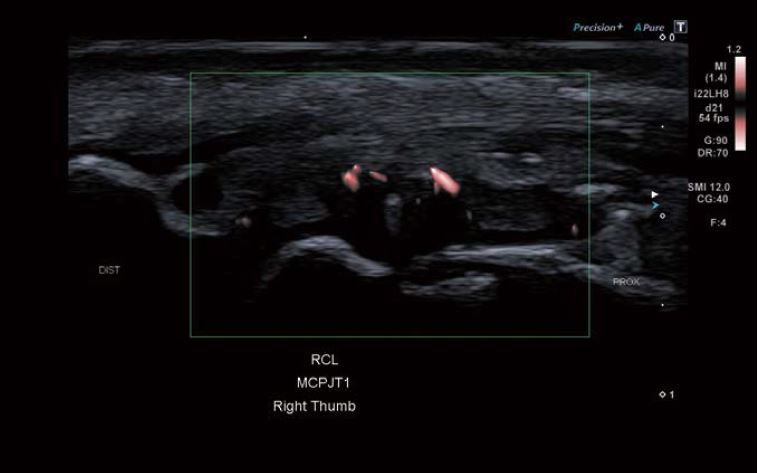

Зображення 4 Суперсудинна візуалізація (SMI) ПКЗ демонструє підвищену васкуляризацію.